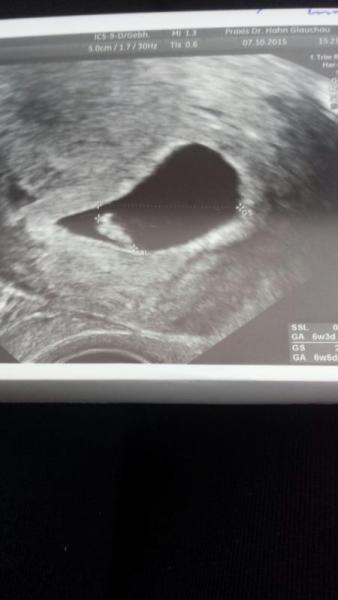

Arzt Besuch war sehr erfolgreich :)))))) Bin heute bei 6+5 SSW. Ich habe heute das Herzchen schlagen sehen. sieht bis jetzt auch alles supi aus. anbei das Bildchen ...

Bild zu Sie aus wie ein Papagei :)))))) - Schwanger - wer noch? Rund um die Schwangerschaft